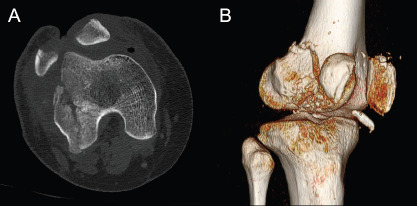

Objective: This study aimed to assess whether three-dimensional (3D) CT imaging improves the inter- and intra-observer reliability of peri-knee fracture classifications, compared to two-dimensional (2D) CT imaging.

Methods: A retrospective analysis was conducted on 23 patients with peri-knee fractures, using both 2D and 3D-CT scans. Three radiologists classified distal femur, patella, and tibial plateau fractures according to Arbeitsgemeinschaft für Osteosynthesefragen/Orthopaedic Trauma Association (AO/OTA) and Schatzker systems. Reliability was measured using Cohen's kappa, with evaluations conducted at two separate intervals to assess intra- and inter-observer consistency.

Abstract Image